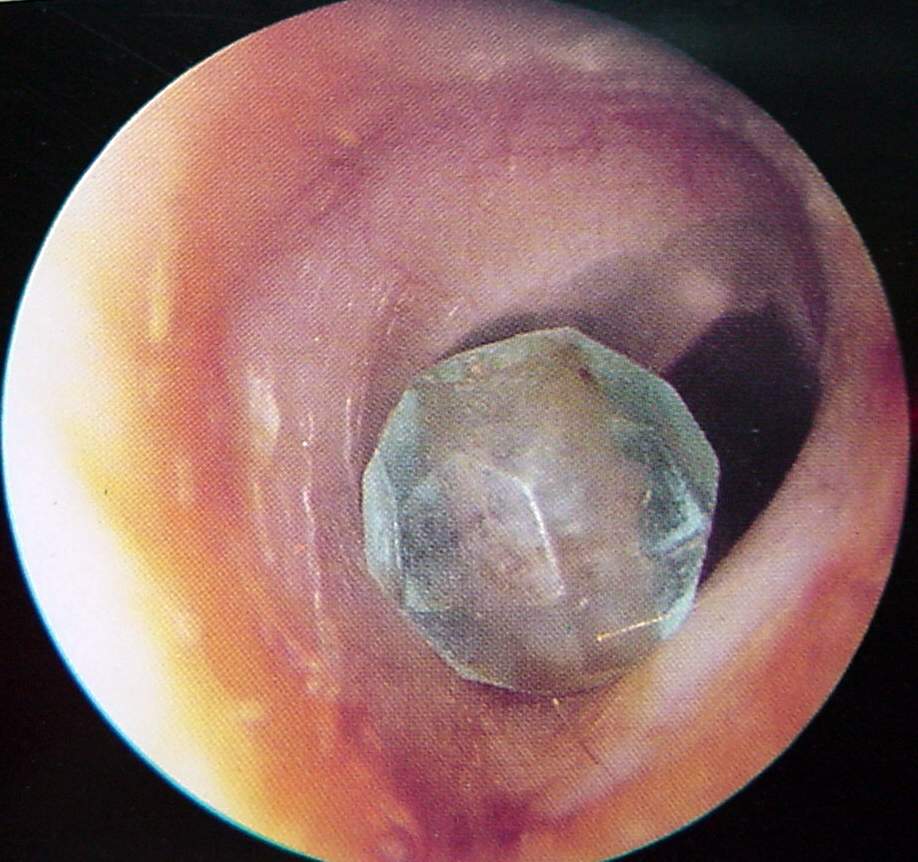

Ear Clinical Photos for Static Stations